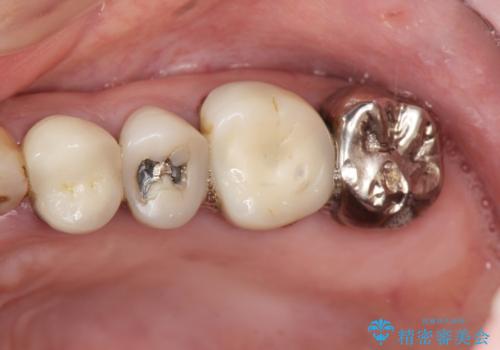

- 左側の奥歯で噛むと痛みや違和感が強く、しっかり噛めない、治療したいと希望され来院されました。

歯周組織検査やX線検査等、精査を行った結果、根尖性歯周炎や不適合なクラウンによる歯茎の炎症、歯の破折等様々な問題が認められました。

根まで破折してしまっている歯は、残すことができないので抜去を行いインプラント治療、

残すことのできる歯は根管治療を行い、精密なセラミック治療を行うこととしました。